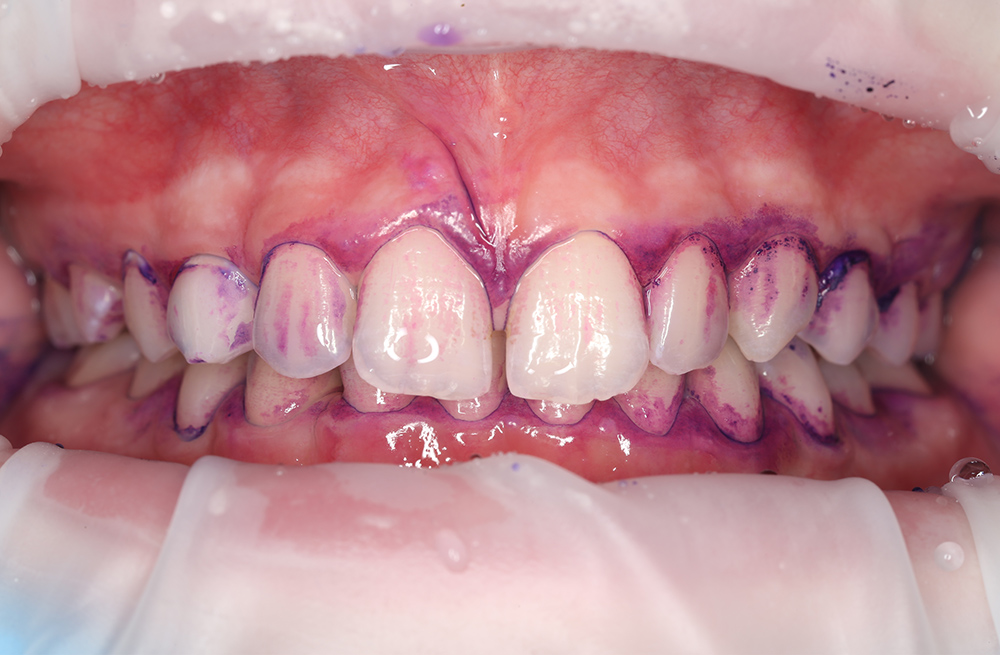

Удаление мягкого и пигментированного налёта у подростка с использованием Air-flow

Эффективная чистка зубов с ортодонтическими конструкциями под контролем стоматолога

Детская чистка зубов с профессиональным уходом ребёнку 10 лет

Чистка зубов Air Flow у ребёнка для профилактики кариеса

Профессиональная гигиена и обучение домашнему уходу за зубами с помощью технологии Air Flow

Первая профессиональная гигиена полости рта у ребёнка с использованием Air Flow

Профессиональная чистка зубов Air Flow с диагностикой и планированием лечения кариеса

Плановая стоматологическая гигиена для подростка 12 лет

Профессиональная чистка зубов подростку 13 лет

Профессиональная чистка зубов с ретейнерами подростку 14 лет